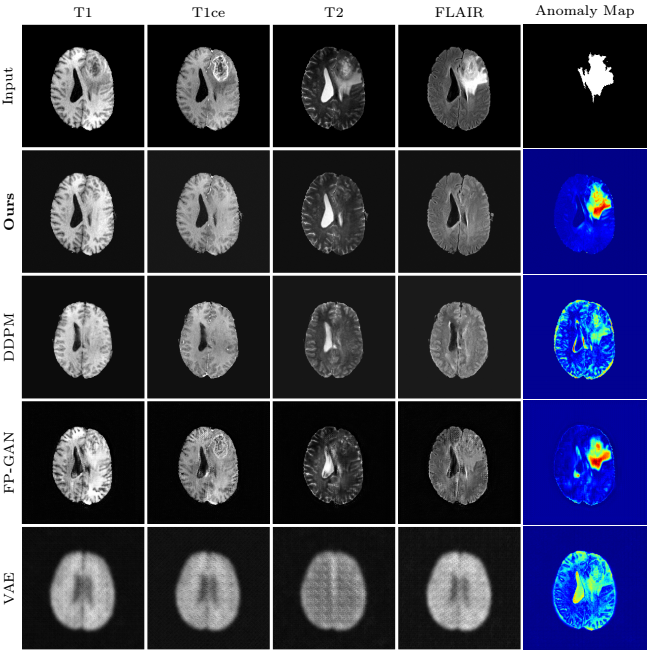

Figure 12. Results for an image of the BRATS2020 dataset for L = 500 and s = 100.

Observations:

- DDIM (ours): Details of the input image can be mainly reconstructed;

- DDPM: The anatomical structure of input changes with the DDPM sampling scheme;

- Only the VAE tries to reconstruct the right ventricle.